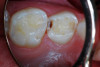

(6.) After exposure of disto-occlusal caries, SDF is applied, followed by a coating of fluoride varnish.

Figure 6

(7.) After exposure of disto-occlusal caries, SDF is applied, followed by a coating of fluoride varnish.

Figure 7

(8.) After exposure of disto-occlusal caries, SDF is applied, followed by a coating of fluoride varnish.

Figure 8